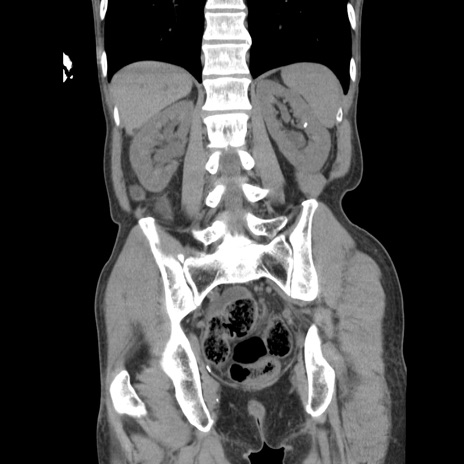

症例11(冠状断像)

【症例】 60歳代男性

【主訴】 下腹部痛

【現病歴】 本日夜中より下腹部痛の症状認め、受診。

【既往歴】 膀胱癌(膀胱全摘+尿管皮膚瘻術) 、胃癌術後

【身体所見】 BT 35.3℃、PR 58/min、BP 136/98mHg、腹部平坦、軟、腸蠕動音±、ストマ留置あり、左上腹部~正中部に圧痛あり、反跳痛なし。

【データ】WBC 5100、CRP0.01